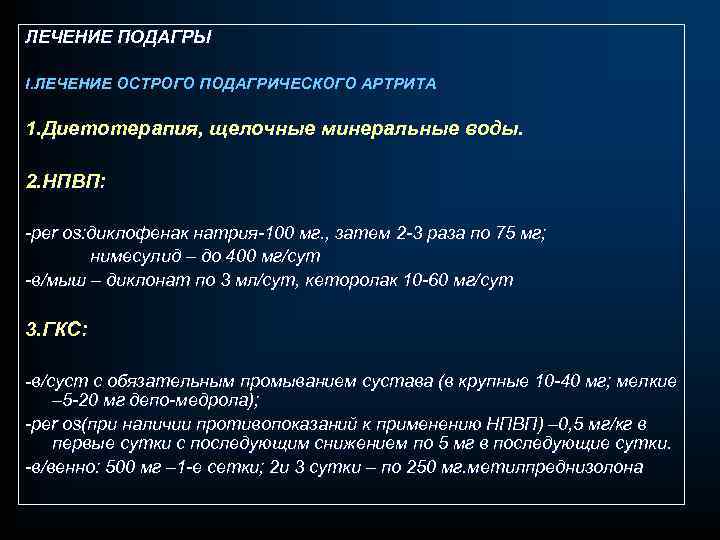

ЛЕЧЕНИЕ ПОДАГРЫ I. ЛЕЧЕНИЕ ОСТРОГО ПОДАГРИЧЕСКОГО АРТРИТА 1. Диетотерапия, щелочные минеральные воды. 2. НПВП: -рer os: диклофенак натрия-100 мг. , затем 2 -3 раза по 75 мг; нимесулид – до 400 мг/сут -в/мыш – диклонат по 3 мл/сут, кеторолак 10 -60 мг/сут 3. ГКС: -в/суст с обязательным промыванием сустава (в крупные 10 -40 мг; мелкие – 5 -20 мг депо-медрола); -реr os(при наличии противопоказаний к применению НПВП) – 0, 5 мг/кг в первые сутки с последующим снижением по 5 мг в последующие сутки. -в/венно: 500 мг – 1 -е сетки; 2 и 3 сутки – по 250 мг. метилпреднизолона

ЛЕЧЕНИЕ ПОДАГРЫ I. ЛЕЧЕНИЕ ОСТРОГО ПОДАГРИЧЕСКОГО АРТРИТА 1. Диетотерапия, щелочные минеральные воды. 2. НПВП: -рer os: диклофенак натрия-100 мг. , затем 2 -3 раза по 75 мг; нимесулид – до 400 мг/сут -в/мыш – диклонат по 3 мл/сут, кеторолак 10 -60 мг/сут 3. ГКС: -в/суст с обязательным промыванием сустава (в крупные 10 -40 мг; мелкие – 5 -20 мг депо-медрола); -реr os(при наличии противопоказаний к применению НПВП) – 0, 5 мг/кг в первые сутки с последующим снижением по 5 мг в последующие сутки. -в/венно: 500 мг – 1 -е сетки; 2 и 3 сутки – по 250 мг. метилпреднизолона